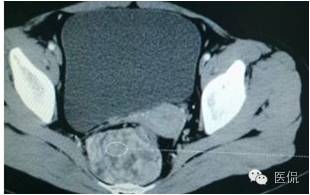

增强动脉期(CT值31HU)